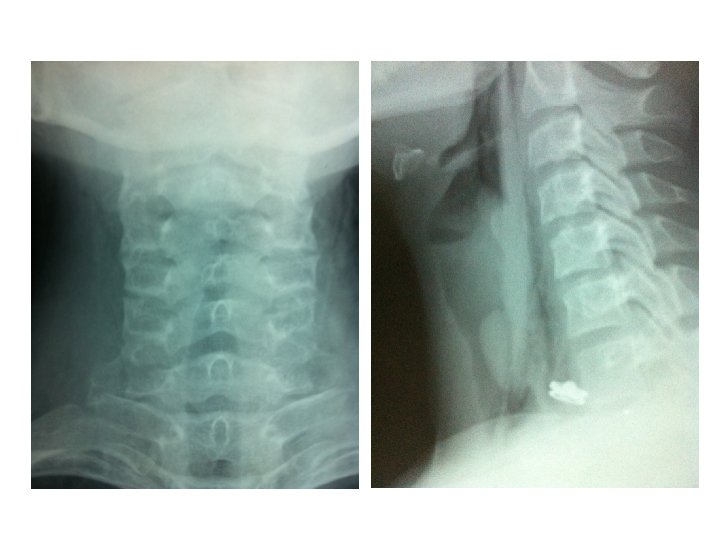

• Examination findings – Respiratory system : Stridor + – Other systems : Normal • Suspected diagnosis: – Post intubation tracheal stenosis